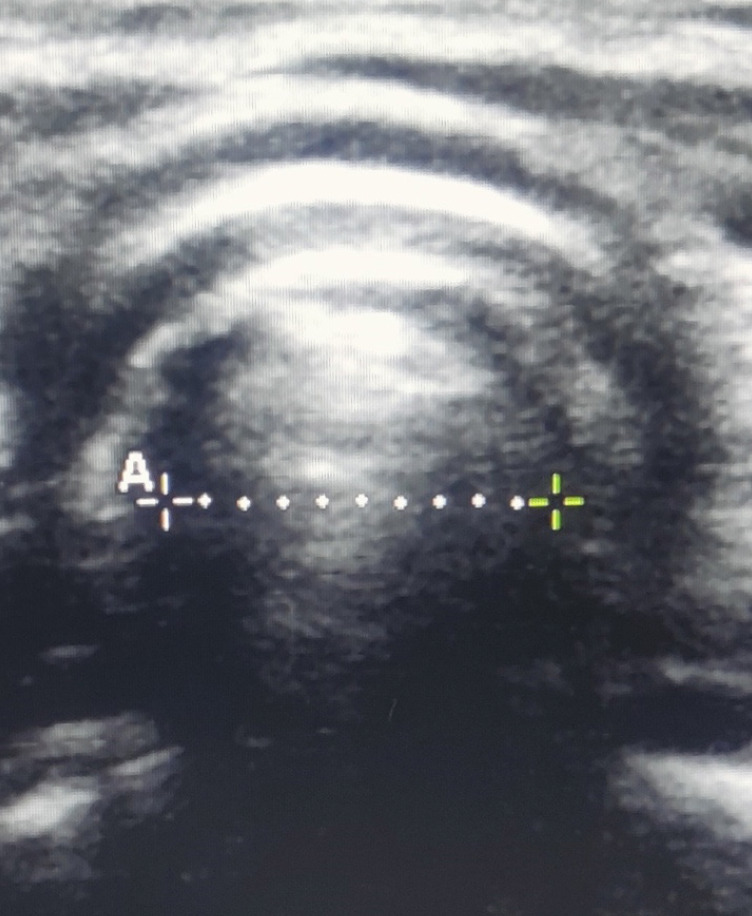

Methods: One hundred eighteen patients, aged 1 to 5 years, with American Society of Anesthesiologists, classifications of I or II, were included. After standard general anaesthesia protocols, the subglottic diameter was assessed by USG. Intubation was performed using ETT size according to age-based formula. The best clinical fit was determined after the leak test. The internal and external diameters of the ETTs were predicted by both methods and correlated with the best-fit ETT sizes used during the procedures using Pearson's correlation. Cohen's kappa was used for statistical agreement between two methods.

目的:在儿科人群中,选择合适尺寸的气管内管(ETT)不仅可以保证足够的通气,而且可以避免拔管后的喘鸣和狭窄。通常,基于年龄、身高或体重的公式被用来确定最合适的尺寸。在这项研究中,我们比较了超声(USG)和基于年龄的公式来预测1-5岁儿童患者的最佳微袖ETT大小。方法:纳入118例年龄1 ~ 5岁的美国麻醉师学会I或II级患者。在标准全身麻醉方案后,用USG评估声门下直径。根据年龄公式使用ETT大小进行插管。通过泄漏试验确定最佳临床匹配。两种方法均可预测导管导管的内径和外径,并使用Pearson相关性与手术过程中使用的最适合的导管导管导管大小相关。Cohen’s kappa用于两种方法之间的统计一致性。结果:与基于年龄的公式相比,USG与最佳拟合模型的相关性显著更高,符合率分别为99.2%和77.1%。最佳拟合ETT与usg指导估计值有较好的相关性(r = 0.994, P < 0.001)。Cohen’s Kappa值为0.986,表明usg指导估价值与最佳拟合ETT之间的一致性具有统计学意义。结论:在1-5岁的儿童年龄组中,usg引导下的声门下直径估计比基于年龄的公式更能预测最佳大小的微袖套ETT。22%的管变可以通过超声引导作为估计ETT大小的主要方法来预防。